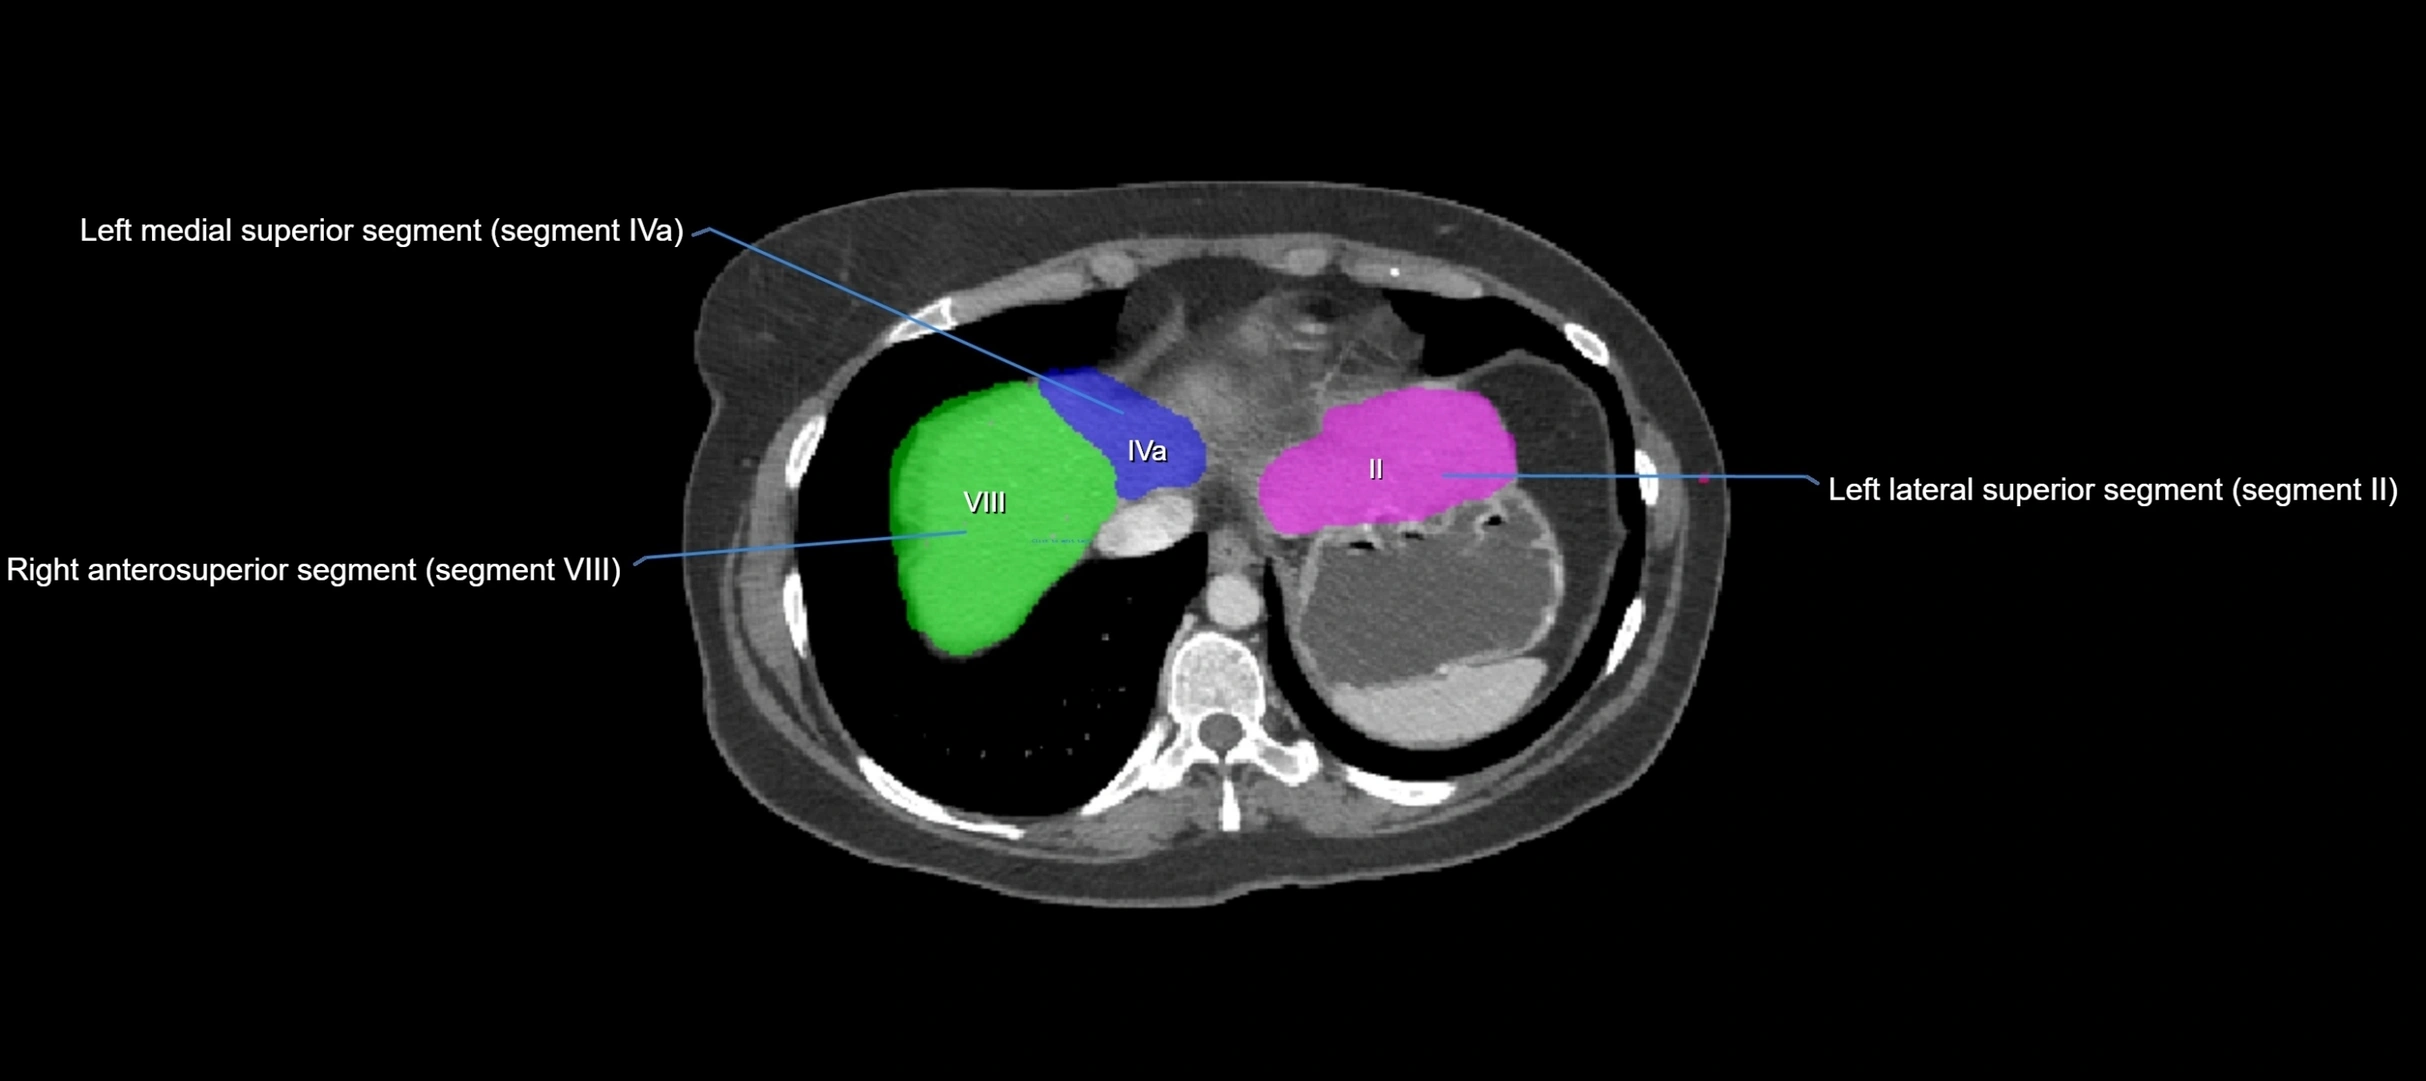

CT Image

image